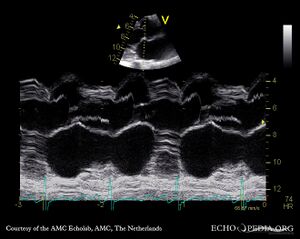

| M-Mode through aortic valve